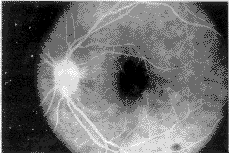

本组218眼中,萎缩型者168眼(77.06%),其眼底表现为黄斑区色素紊乱,中心凹反光消失 ,有散在分布大小不等的黄白色玻璃膜疣,以软性为主,且相互融合成团.色素上皮或脉络 膜毛细血管萎缩区呈灰绿色地图状.荧光眼底血管造影显示:在动脉期即呈现斑点状荧光, 这些斑点荧光恰位于眼底玻璃膜疣或色素上皮脱色素部位,成为典型的“帘样”荧光,见图 1.

图1 造影动脉期黄斑部“帘样”荧光

在静脉期后斑点状荧光随背景荧光增强而加亮,形态大小不变.造影后期随背景荧光逐渐减 弱而变淡,见图2.

图2 造影晚期黄斑部荧光

部分病例背景荧光消退后可见荧光斑点仍清晰存在,但整个造影过程中荧光形 态、大小不变 .我们认为此情况为玻璃膜疣着色所致.本组病例中,发现造影见到的玻璃膜疣往往比眼底 所见的较多,说明眼底检查不能完全了解眼底病变之全貌.部分病例在造影初期出现圆形或 不规则圆形荧光斑,中期加强但形态不扩大,晚期荧光逐渐消退.分析这种荧光形态可能是 因色素上皮下沉着物堆积而造成小范围的色素上皮脱离,但其间无浆液充填也无染料渗漏现 象,故证明无新生血管.